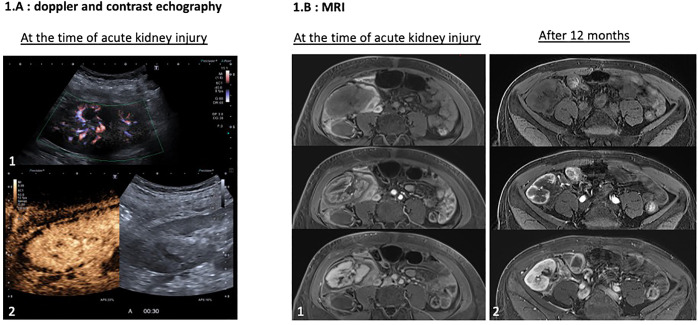

Catastrophic antiphospholipid syndrome (CAPS) leads to organ dysfunction due to thrombotic microangiopathy (TMA). Complement may play a role in CAPS, and its blockade could prevent antiphospholipid syndrome (APS) complications after kidney transplantation (KT). Here, we report a case of APS recurrence after KT in a 38-year-old woman with early acute cortical kidney allograft necrosis despite preventive eculizumab treatment, probably because of insufficient complement blockade. The patient had recurrent but controlled CAPS for years with renal dysfunction, leading to preemptive KT. Anticoagulation and eculizumab were administered to prevent thrombosis and TMA after KT. She developed acute kidney injury (AKI) with incomplete biological TMA. Imaging revealed cortical necrosis in the renal allograft. In the absence of donor-specific anti-HLA antibodies, we concluded a relapse. Additional doses of eculizumab and plasma exchange allowed the normalization of biological tests and improvement of kidney allograft function. A retrospective complement analysis showed an incomplete blockade at the time of AKI. One year after KT, the renal allograft function was impaired. This suggests that inadequate complement blockade leads to a relapse of APS in the renal allograft with cortical necrosis and dysfunction. Our case highlights the importance of monitoring complement activity and adjusting the dose of eculizumab or ravulizumab.